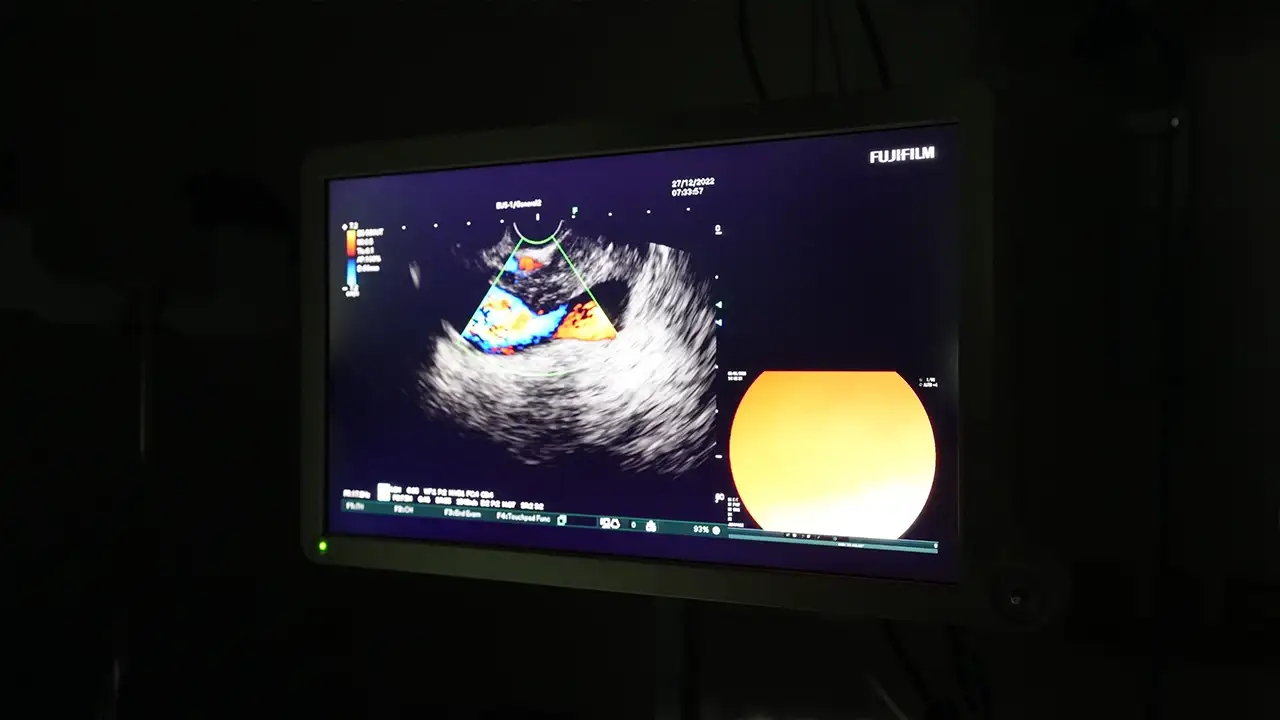

Trabzon’da sağlık alanında önemli bir adım daha atıldı. Trabzon Kanuni Eğitim ve Araştırma Hastanesi bünyesinde ileri endoskopik tanı yöntemlerinden biri olan Endoskopik Ultrasonografi (EUS) işlemi uygulanmaya başlandı.

Gastroenteroloji Uzmanı Dr. Recep Ayhan, EUS işlemini hastanede başarıyla gerçekleştirmeye başladı.

EUS yöntemi sayesinde; özofagus ve mide submukozal lezyonları, pankreas kitle ve kistleri ile koledok lezyonlarının tanısı yapılabiliyor. Sindirim sistemi ve çevresindeki organların detaylı şekilde görüntülenmesine imkân tanıyan bu yöntem, hastalıkların daha doğru ve erken teşhis edilmesine katkı sağlıyor.

“Endoskopik Ultrasonografi; özellikle pankreas ve sindirim sistemi kaynaklı hastalıkların tanısında son derece önemli bir yöntemdir. EUS sayesinde lezyonlar detaylı şekilde değerlendirilebilmekte, gerekli durumlarda hedefe yönelik biyopsi alınabilmektedir.” dedi.